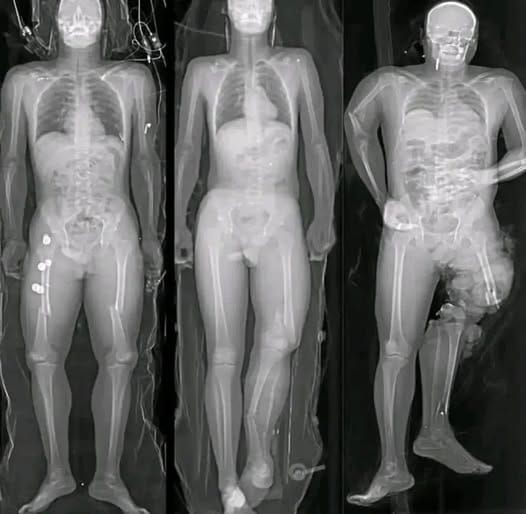

Medical research has identified a small number of myocarditis cases—an inflammation of the heart muscle—following certain mRNA vaccines, particularly among adolescent and young adult males. However, context is critical. These cases are rare, typically mild, and most individuals recover fully with minimal treatment.

Multiple peer-reviewed studies show that the risk of myocarditis from COVID infection itself is significantly higher than the risk associated with vaccination. COVID-19 as a disease has been linked to more severe cardiac complications, including inflammation, blood clots, and long-term heart damage.

In other words, when comparing risks, vaccination reduces overall heart-related danger rather than increasing it.